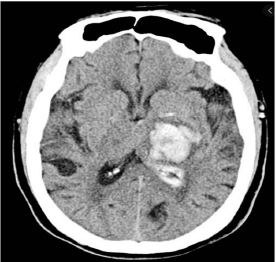

Paciente de 66 anos do sexo feminino com antecedente de hipertensão, AVC hemorrágico há 2 anos sem sequelas, e arritmia, sem seguimento médico adequado, fazendo uso irregular de captopril. Além disso, apresentou traumatismo craniano leve na semana passada, sem maiores repercussões.

Procura pronto-socorro com queixa de déficit neurológico agudo, com aparecimento há 40 minutos. À admissão, exibe PA 150x92, FC 77, FR 18, SatO2 96% a.a., glicemia capilar de 90mg/dL. Ao exame neurológico, apresenta hemiplegia à direita, afasia global e paralisia facial de padrão central, com NIHSS = 15. Realizada TC de crânio, abaixo:

Neste momento, a conduta mais adequada para essa paciente seria